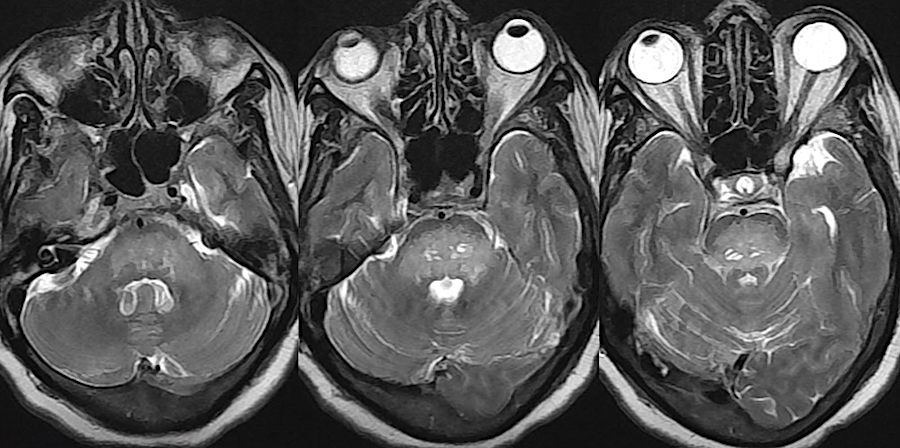

- Проводится компьютерная томография.

- Врач может использовать магнитно-резонансную диагностику.